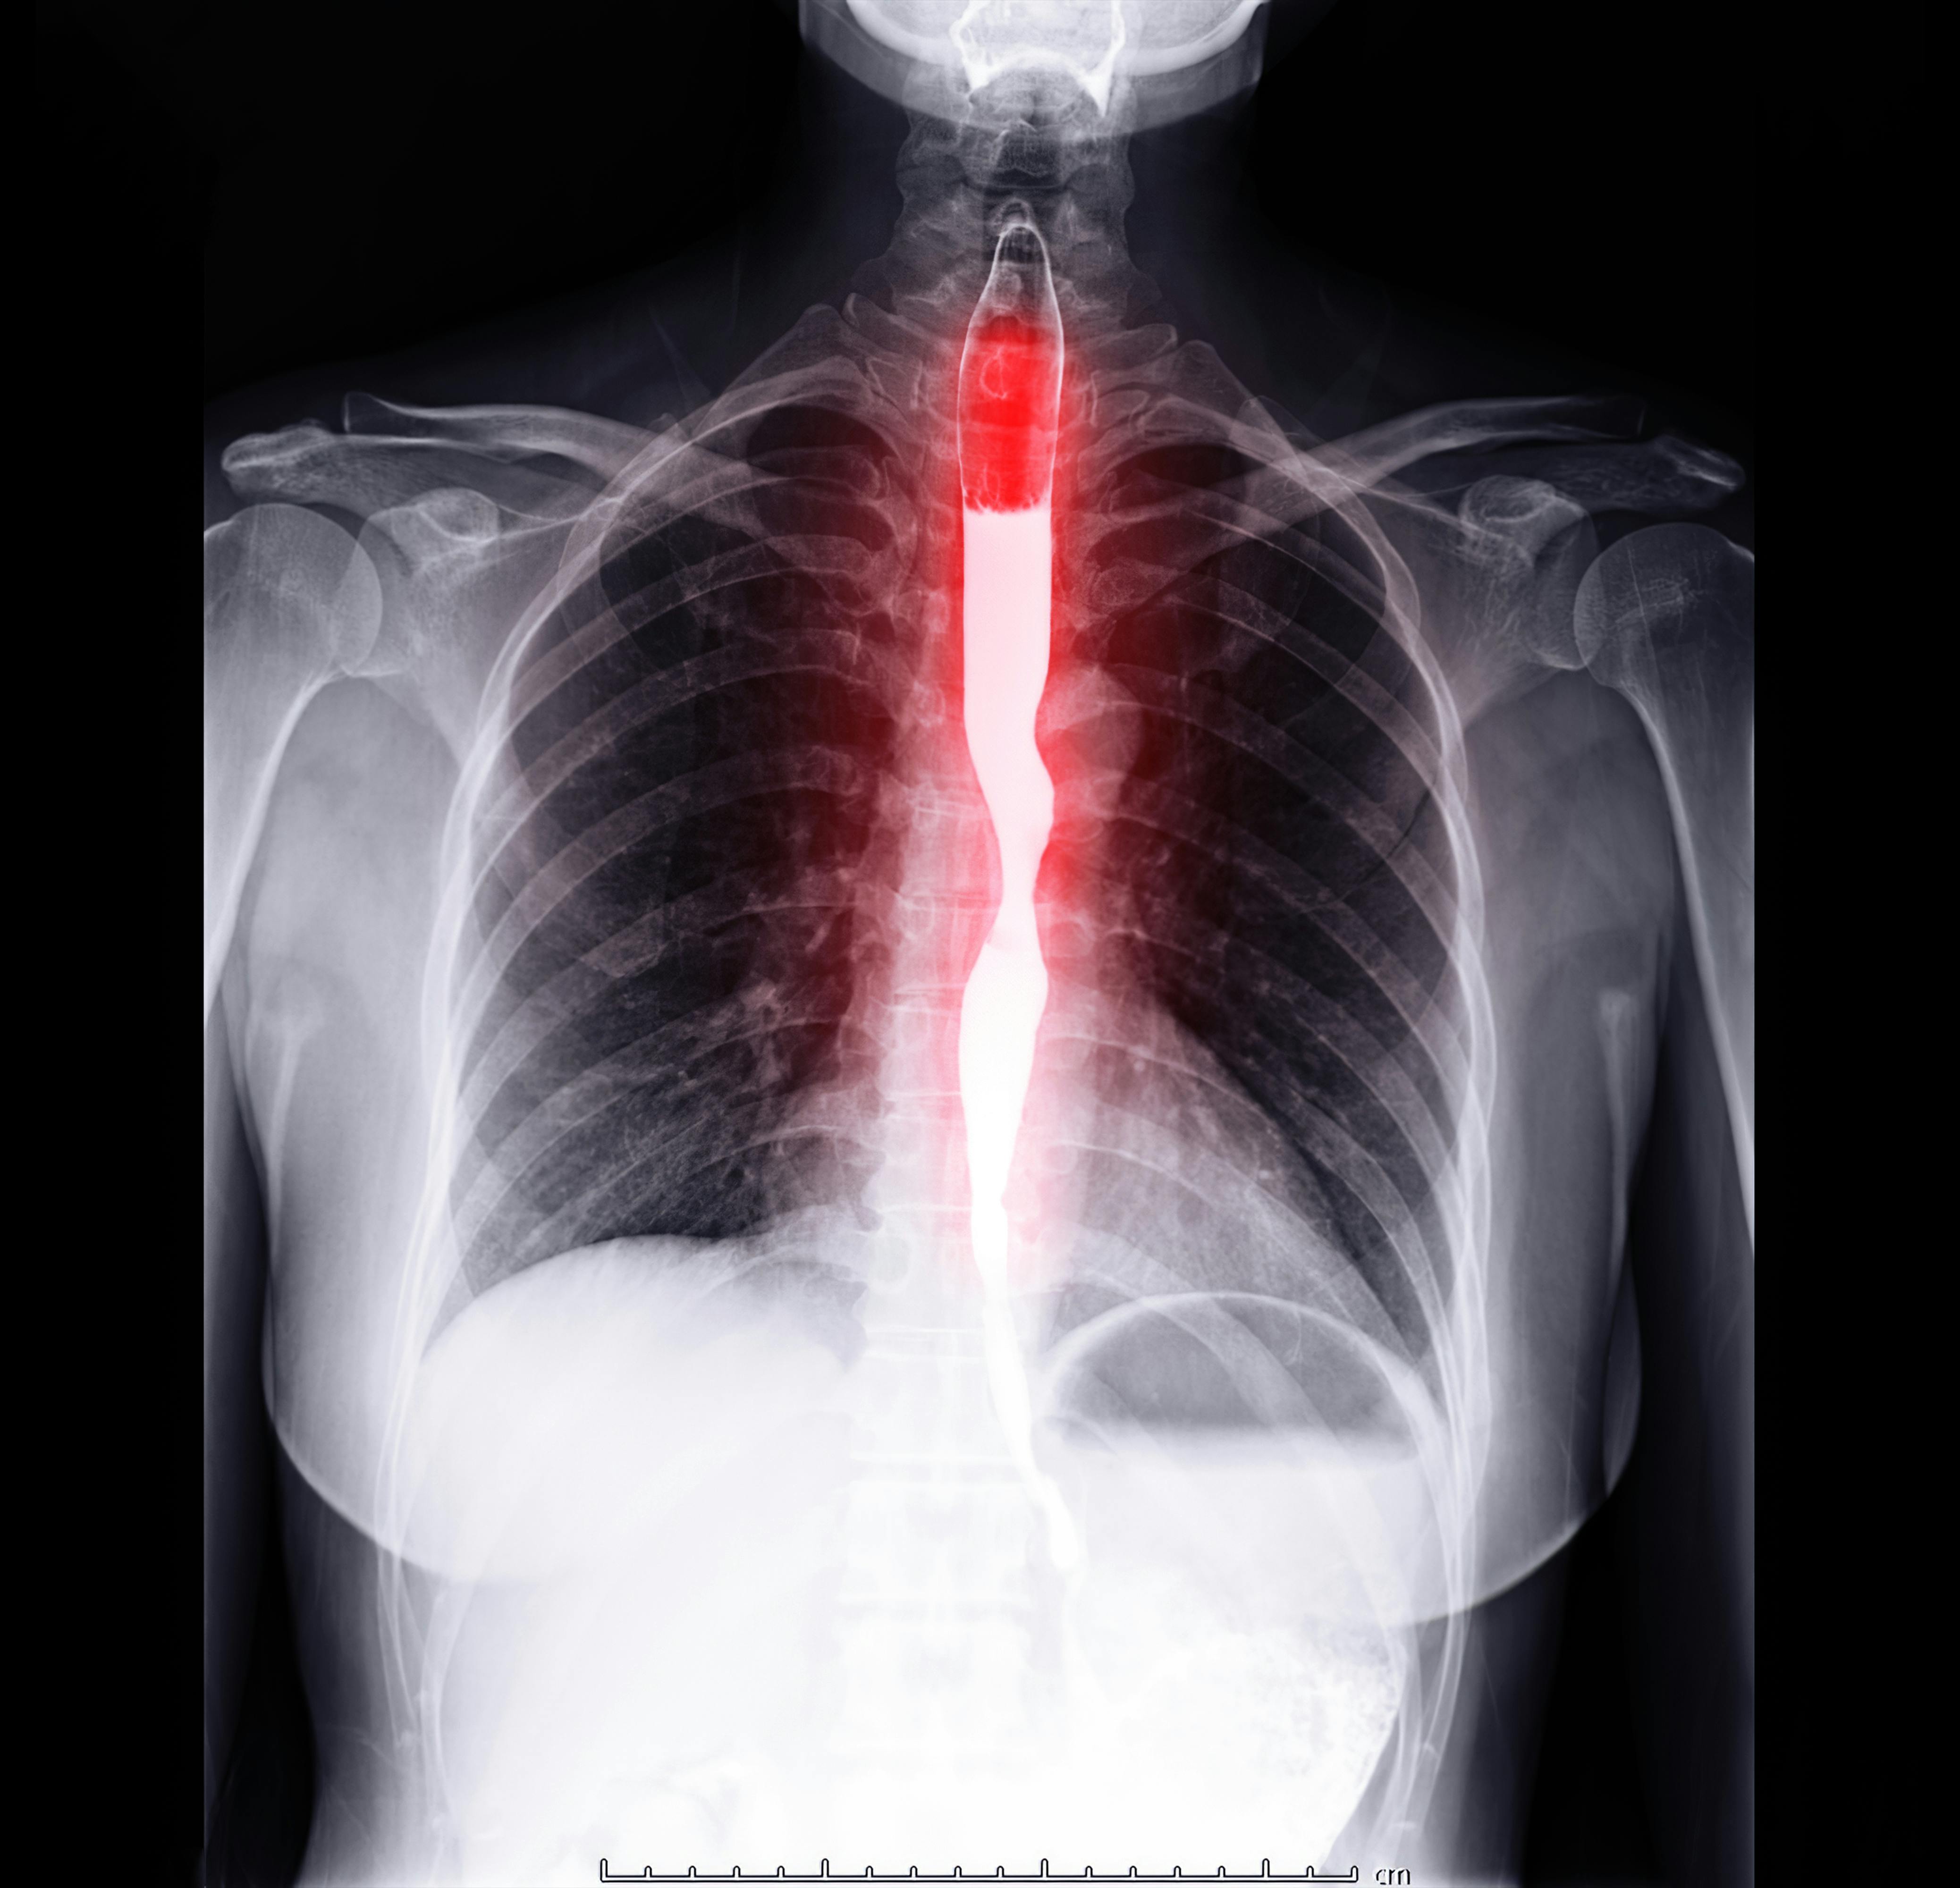

A novel test developed by Johns Hopkins Kimmel Cancer Center investigators could give gastroenterologists insight into which patients with Barrett’s esophagus are likely to progress to esophageal cancer or an abnormal collection of cells called high-grade dysplasia.

This information could help physicians determine how to monitor or manage patients during clinical care.

The test, called Esopredict, is a PCR (polymerase chain reaction)-based laboratory test that, from biopsy samples, measures the level of DNA methylation changes in the genes RUNX3, p16, HPP1 and FBN1. Methylation changes often occur early during abnormal cell growth, before conditions can be detected clinically. By combining these results with patients’ age, physicians can gauge the likelihood that patients’ premalignant conditions will advance and help them determine how often to monitor or manage patients with potential neoplastic progression.

Using the tool in previously collected biopsies from 240 patients with Barrett’s esophagus from six medical centers, researchers determined that the overall risk for neoplastic progression was 5.1%. Patients in the highest risk group had a 21.7% risk of developing high-grade dysplasia or esophageal cancer, compared with a 6.87% risk among those in the high moderate group, a 3.25% risk for those in the low moderate group and just 1.27% among those in the lowest risk group. A description of the work was published online August 14 in The American Journal of Gastroenterology. The test is now commercially available.

Researchers ran the Esopredict test on 209 biopsy samples previously collected from patients with Barrett’s esophagus at Johns Hopkins and Allegheny Health Network, Capital Digestive Health, Mayo Clinic, University of Maryland and University of Connecticut healthcare sites. The first 99 patient samples served as a training set in which a model algorithm was designed, and the next 110 patient samples were analyzed as a validation set in which the algorithm was tested. Samples also were assayed from an additional group of 31 patients who went on to develop high-grade dysplasia or esophageal cancer and who had follow-up intervals longer than five years.

Some 78 of the 209 patients progressed to having high-grade dysplasia or esophageal cancer within five years of biopsy collection, while the remaining 131 had no progression over the next five years. Investigators ran several calculations with Esopredict to try to predict the likelihood of cancer or high-grade dysplasia developing. They stratified patients into two main groups: lower risk (further refined into low and low-moderate risk categories) or higher risk (further refined into high moderate or high-risk levels) of progressing to more serious conditions. Overall, they found that patients in the two higher risk groups to be 6.4 times more likely to progress to high-grade dysplasia or esophageal cancer within five years. Compared with patients considered lowest risk, the highest risk patients were 15.2 times more likely to progress to these more serious conditions.